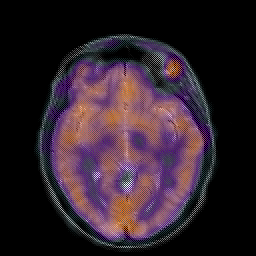

Hypertensive Encephalopathy, overlay -- Slice #11

[Home][Help][Clinical] Slice 11